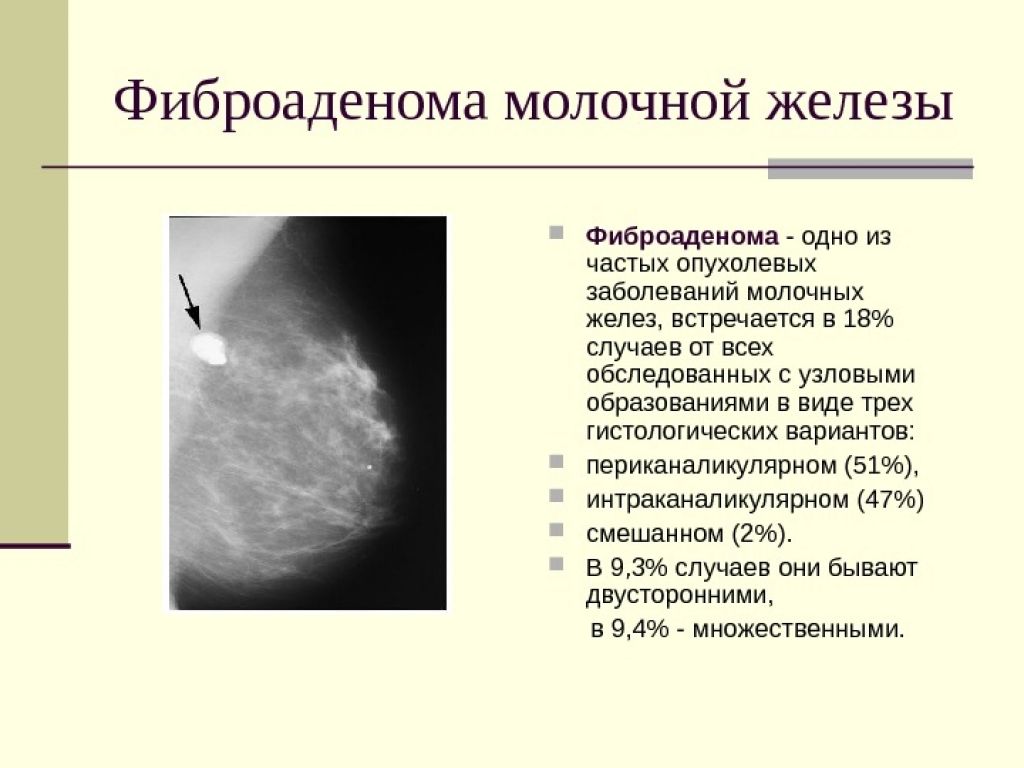

Уплотнения в груди могут быть вызваны различными причинами, включая кисты, фиброаденомы или инфекционные процессы. Важно понимать, как правильно подходить к их лечению и когда обращаться к врачу. Следующие советы помогут вам разобраться в этом вопросе и обеспечить здоровье своей груди.